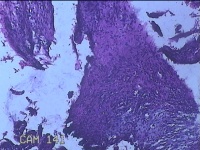

左大腿内侧包块

性别

男

年龄

21岁

临床诊断

脂肪瘤

一般病史

左大腿内侧起包块一月余。

标本名称

大体所见

灰白暗红色包块2.5x2x0.8cm一个,表面糜烂,切开包块呈实性,切面灰白暗红色,质软。

片子这个效果,没有胆量下诊断了。

脱水机的试剂多久没有更换了?